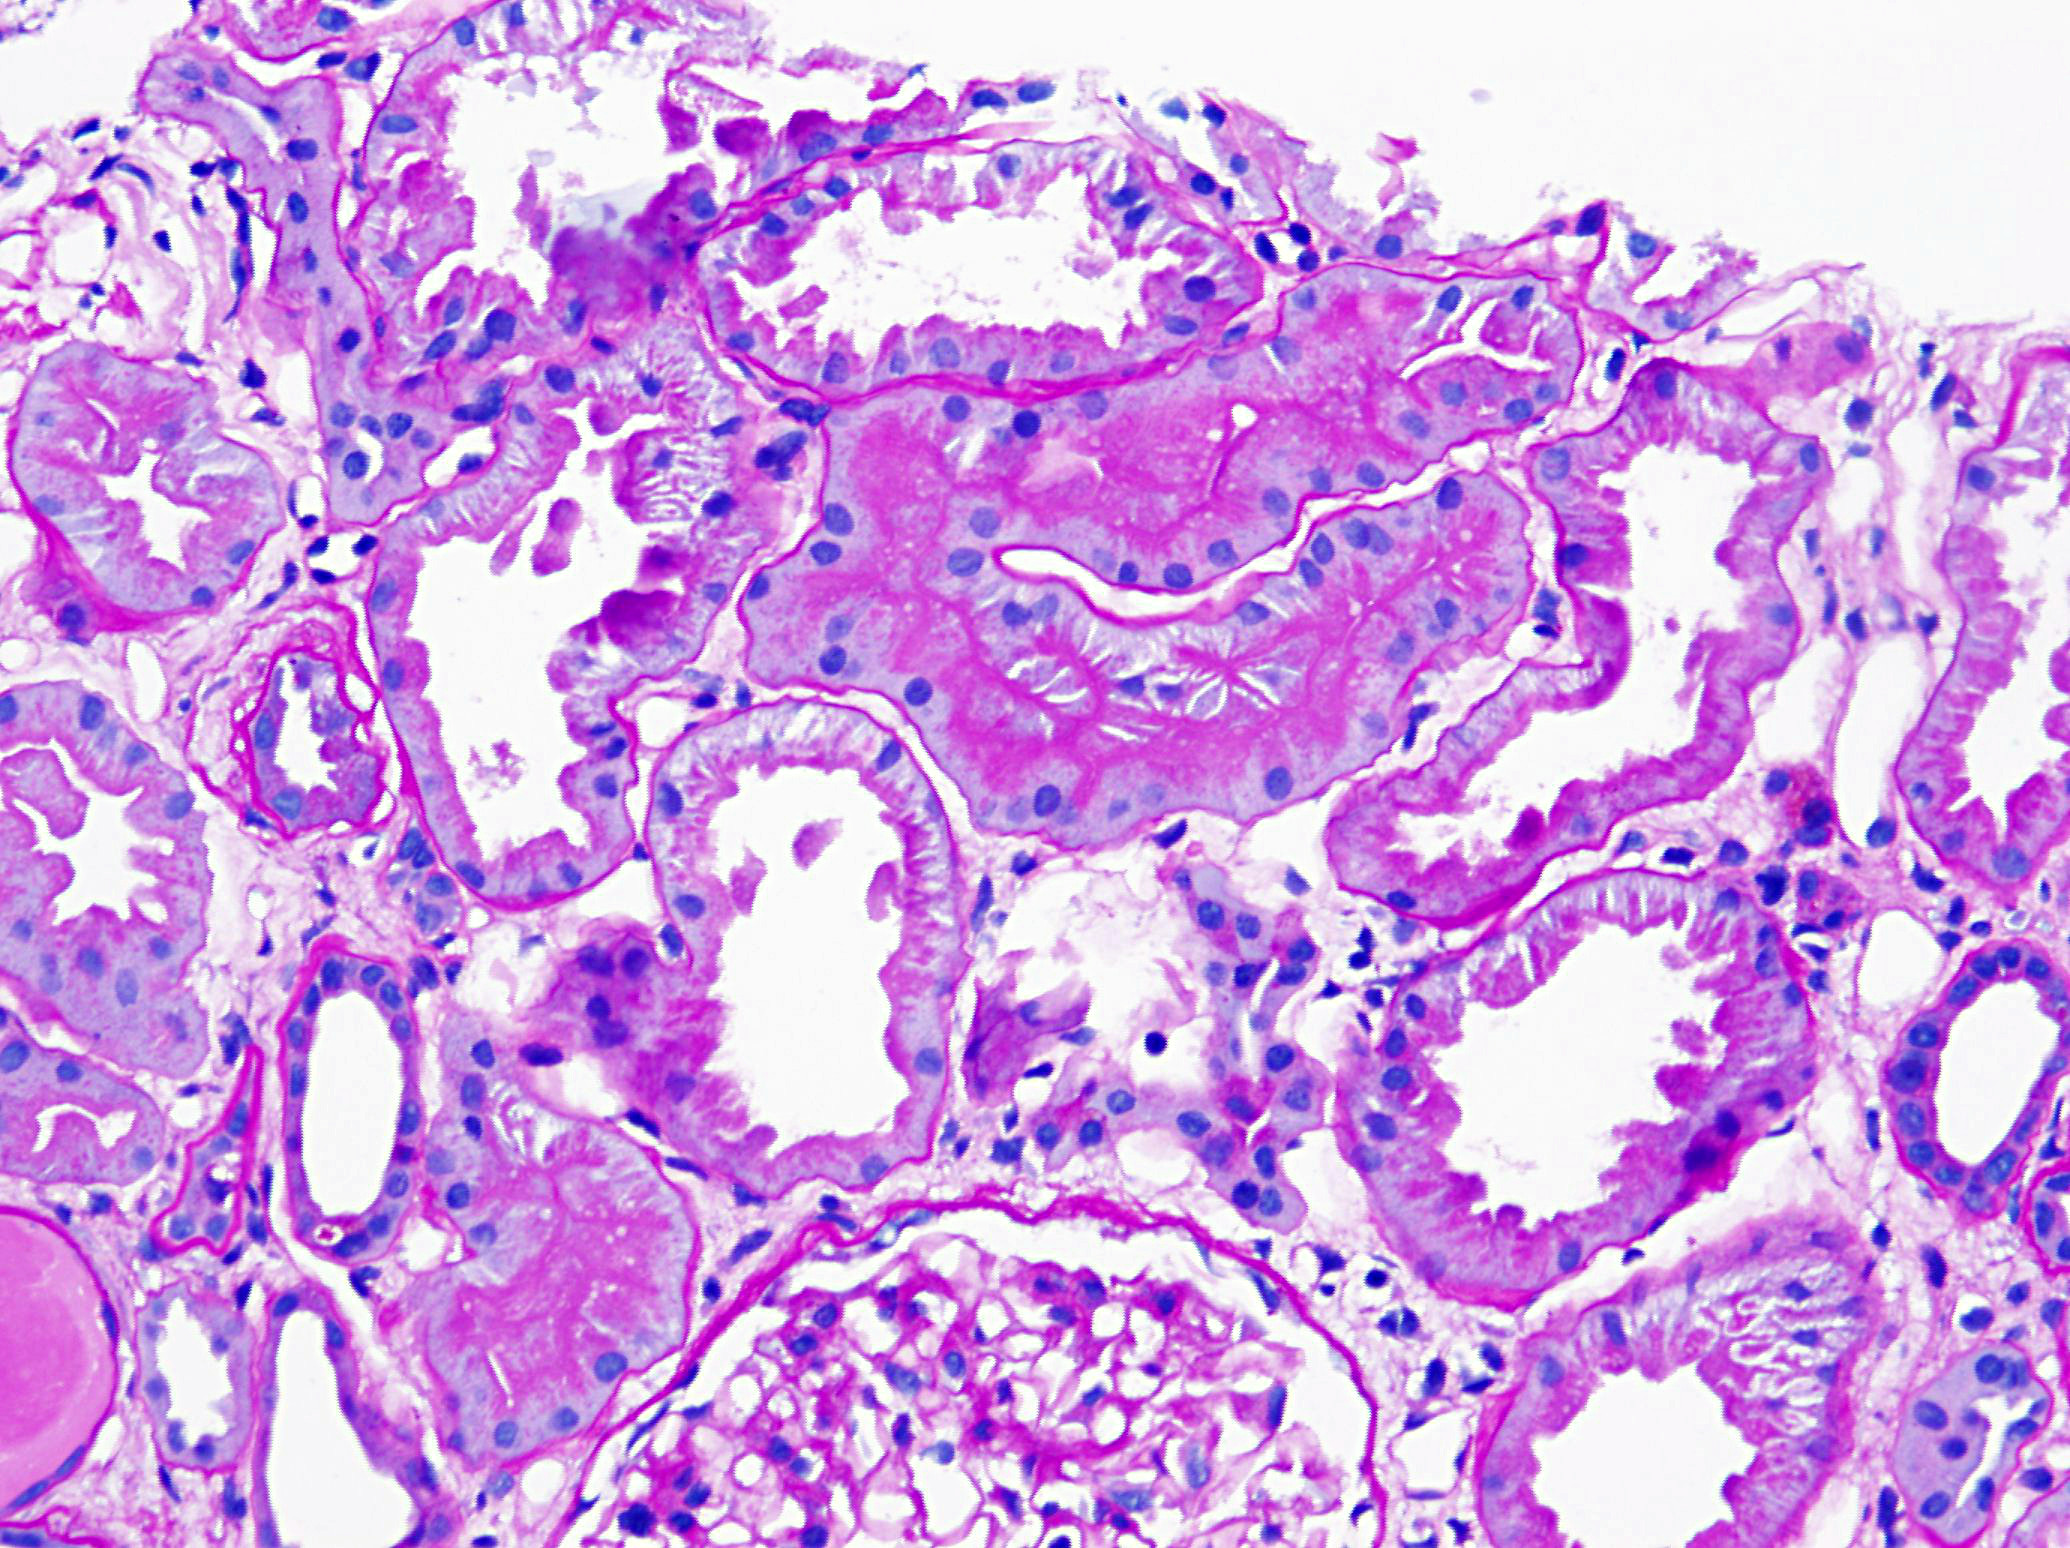

A 71-year-old man with long standing history of hypertension presented with increased serum creatinine of 3.4 mg/dL, detected during routine laboratory examination, with no associated symptoms. He was eventually seen by a nephrologist. A kidney biopsy was performed. The biopsy findings are shown in the following figures (Fig A & B: PASH stain, Fig C: Lambda- immunofluorescence stain, Fig D: Kappa- immunofluorescence stain and Fig E: Electron Microcopy of the proximal epithelial cell cytoplasm).

The diagnosis of monoclonal immunoglobulin deposition disease (MIDD) by renal biopsy often precedes other clinical evidence of dysproteinemia and is commonly the presenting disease, which leads to the discovery of multiple myeloma. The renal diseases most frequently associated with multiple myeloma/MGUS include; amyloidosis, light chain deposition disease (LCDD) and light chain cast nephropathy (LCCN). Less frequently reported is a light chain proximal tubulopathy (LCPT) characterized by kappa-restricted crystal deposits in the proximal tubular epithelial cells cytoplasm. These patients classically present with Fanconi syndrome in the setting of smoldering myeloma. Light chain proximal tubulopathy without crystal formation, on the other hand, is relatively rare and under recognized dysproteinemia related entity which by light microscopy shows nonspecific pattern of acute tubular injury with no significant casts or crystal formation (Fig A and B). However monoclonal staining of protein resorption droplets within proximal tubular epithelial cells, by immunofluorescence, provides clue to the diagnosis (Fig C and D). Electron microscopy shows increased lysosomes with irregular contours and mottled appearance within proximal tubular epithelial cells (Fig E).